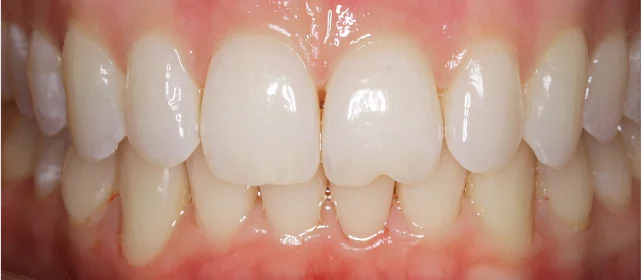

Зубы выровнены, смыкание нормализовано. Установлены несъёмные ретейнеры на обе челюсти, изготовлены ретенционные капы. Пациентка предварительно проконсультирована ортопедом онлайн.

Решение: Поставили элайнеры 3D Smile на обе челюсти. Лечение заняло 4 года и потребовало нескольких последовательных этапов коррекции. Капы менялись каждые 1–2 недели, на контрольных визитах отслеживали прогресс и выдавали новые наборы. Зубы встали в правильное положение, смыкание нормализовалось. Зафиксировали ретейнеры на обе челюсти, изготовили ретенционные капы. Пациентка прошла онлайн-консультацию с ортопедом для оценки дальнейших шагов.